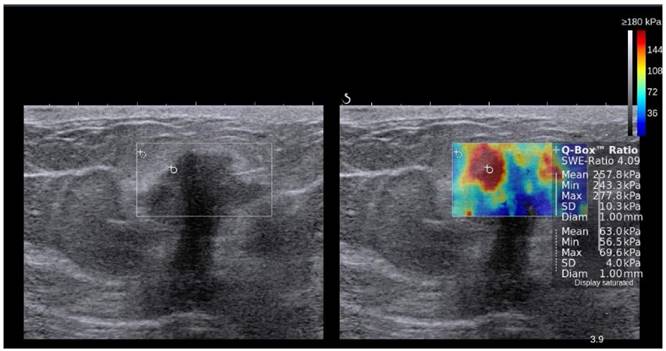

Figure 9

Transverse B-mode image (left) shows small heterogeneous thyroid nodule (lesion within region of interest) with ill-defined margins and microcalcifications in the right thyroid lobe, suggesting malignant etiology. Corresponding color elastogram obtained with 2D-SWE on a Toshiba Aplio 500 (right) shows increased stiffness in the nodule (pink ROI; 32.7 kPa) compared to surrounding normal parenchyma (white ROI; 7.4 kPa), suggesting that the nodule is malignant. Subsequent biopsy confirmed papillary carcinoma.

Theranostics Image

A recent prospective study specifically addressed the question of whether 2D-SWE could distinguish between benign and malignant follicular thyroid neoplasms (Table 3, [78]). In this work, 35 patients with thyroid nodules that had an FNA diagnosis of follicular neoplasms were assessed with B-mode US and 2D-SWE prior to surgery. Although B-mode US features were not predictive of follicular malignancy, higher Young's modulus estimates were associated with follicular malignancy (AUC = 0.81, cut-off value = 22.3 kPa, sensitivity = 82%, specificity = 88%, positive predictive value = 75%, negative predictive value = 91%) [78].